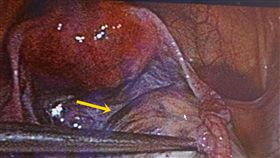

巧克力囊腫作祟 女子結婚5年仍不孕

31歲陳姓女患者,結婚5年多卻一直無法受孕,因先生是...